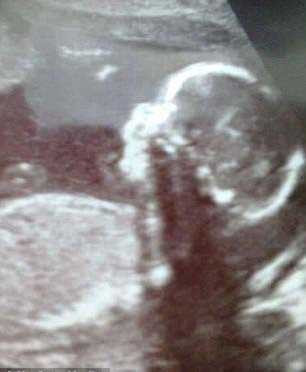

Dünya bu çocuğu konuşuyor. İngiltere'de burnu olağandan buyük doğan bebek dünyanın ilgi odağı oldu..

Ollie Trezise. Trezise ailesinin en küçük ferdi. İngiltere'de yaşayan Trezise ailesi dünyanın gündemine oturdu. Amy Poole'nun doğurduğu bebeğin burnu olağandan büyüktü. Çünkü beyniyle ilgili bir hastalığı vardı.

Tıbben bir ensafelosel hastalığı olan çocuğun beyniyle ilgili hastalığı var. Beynin salgıladığı sıvı vücudun bir yerinden patlak veriyor. Ollie'nin de burnunun ortasından patlak vermiş.